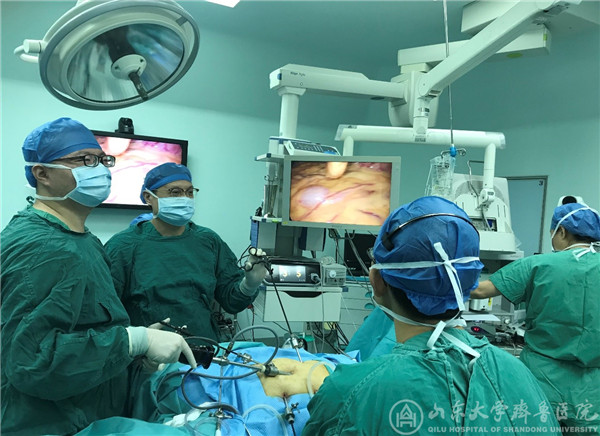

【本站讯】 近日,我院肛肠外科王加勇主治医师在戴勇主任、姜金波教授指导下,成功实施我院首例腹腔镜下结肠癌肝转移一期切除和保留回盲部结肠次全切除NOSES手术。

患者一,女性46岁,术前诊断为乙状结肠癌并肝转移;患者二,男性,65岁,术前诊断为结肠慢传输型便秘。在完善术前检查及充分的术前准备之后,在高磊医师、梁亚航医师、肝脏外科杜刚医师、麻醉科、手术室人员的协助下,分别成功完成腹腔镜下结肠癌肝转移一期切除和保留回盲部结肠次全切除NOSES手术。手术过程顺利,术中基本无出血,手术标本经直肠及肛门取出,腹部无辅助切口。

我院肛肠外科坚持对外交流与学习,把握学科潮流前进方向,紧跟国际、国内前沿,已开展数十例腹腔镜结直肠癌NOSES手术,但肠癌肝转移一期切除NOSES手术和保留回盲部结肠次全切除NOSES手术尚属首例,标志着我院在微创外科领域更前进了一步。